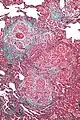

| High magnification photomicrograph of a lung biopsy taken showing chronic hypersensitivity pneumonitis (H&E), showing mild thickening of the walls of the small air sacs by invasion of white blood cells. A multinucleated giant cell, seen within the walls of the air sacs to the right of the picture halfway down, is an important clue to the correct diagnosis. | |

Lung biopsy

Lung biopsies can be diagnostic in cases of chronic hypersensitivity pneumonitis, or may help to suggest the diagnosis and trigger or intensify the search for an allergen. The main feature of chronic hypersensitivity pneumonitis on lung biopsies is expansion of the interstitium by lymphocytes accompanied by an occasional multinucleated giant cell or loose granuloma.[7][22]

When fibrosis develops in chronic hypersensitivity pneumonitis, the differential diagnosis in lung biopsies includes the idiopathic interstitial pneumonias.[23] This group of diseases includes usual interstitial pneumonia, non-specific interstitial pneumonia and cryptogenic organizing pneumonia, among others.[7][22]